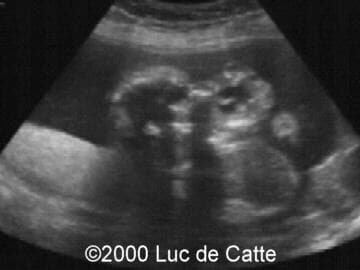

The following structural defects were observed:

• anterior mass,

• emanating from the fetal mouth,

• partly cystic, partly solid

• no calcifications

This 32-year-old primigravida patient was referred at the ultrasound department at 19.5 weeks of gestation for a second opinion concerning a fetal facial mass. Scanning revealed a large, mixed tumor emanating from the pharynx and mouth. The fetal position did not allow for other congenital anomalies to be observed. The diagnosis of epignathus was made.

Epignathus (from the greek epi = above and gnaqos = jaw) represents a rare congenital teratoma arising from the palate or pharynx in the region of the sphenoid (Rathke's pouch)1,2. It may involve the sphenoid bone, pharynx, tongue and jaw. Although it may vary greatly in size and texture, epignathus generally extends through the mouth and creates an anterior facial mass. There is no known genetic or recurrence risk or predisposing factors.

Most are diagnosed by ultrasound scanning in the late second and third trimesters, although early diagnosis at 151 and 17 weeks of gestation3 have been reported. A large mixed solid-cystic and sometimes calcified tumor projecting from the oral cavity suggests the diagnosis. Because the tumor can interfere with swallowing, polyhydramnios can be present3. Occasionally, a large and vascular epignathus may lead to high-output cardiac failure and subsequently to a non-immune hydrops fetalis.